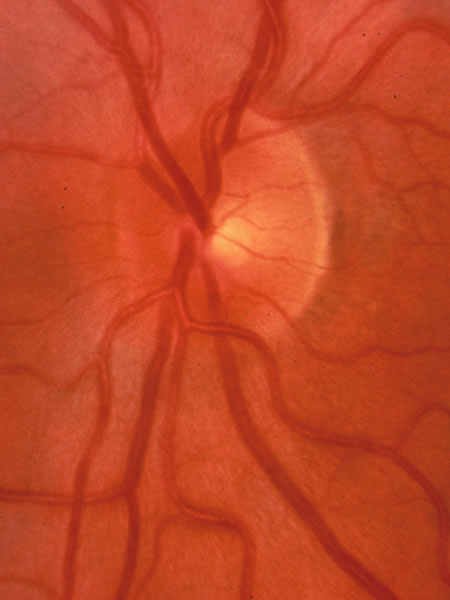

The approximately 1 to 1.5 million axons that form the optic nerve arise from the retinal ganglion cells and course toward the optic disc in a well-known pattern (Fig. 1). From the nasal retina the fibers take a straight course toward the disc. Axons originating temporal to the fovea arc around the macula to enter the upper and lower poles of the optic nerve head. The macula fibers pass directly to the temporal quadrant of the disc in the papillomacular bundle.

Fig. 1. Fundus photograph shows the normal pattern of the retinal nerve fiber layer. (Courtesy of P. Juhani Airaksinen, MD).